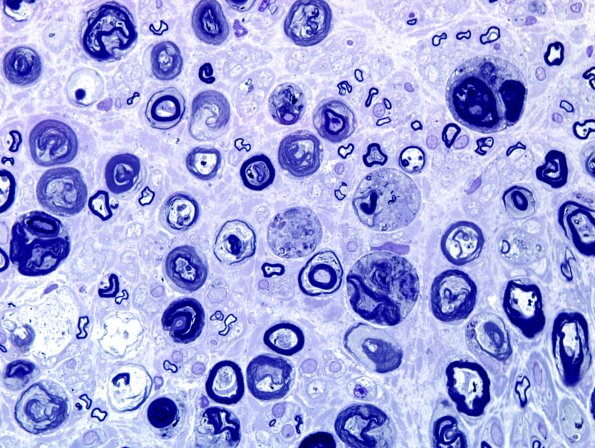

Washington University Experience | PERIPHERAL NEUROPATHY | 4 AXONAL DEGENERATION | 2 Plastic Sections | 9A3 Axonal degeneration, active (Case 9) Plastic 13.jpg

Partially longitudinal sections and cross sections of degenerating axons.